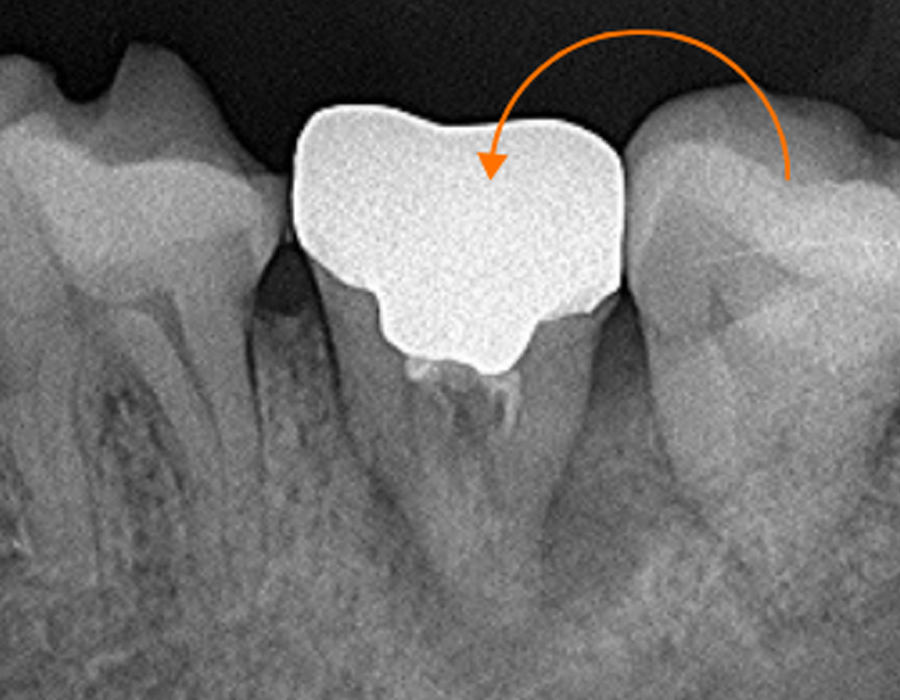

診療案内 medical information ホーム 診療案内 当院の治療のご案内 虫歯治療なるべく虫歯以外の部分を削らないようにし、患者様にも確認してもらいながら治療を進めます。もっと見る 予防歯科 (PMTC) 虫歯の早期発見のためにも当院は定期的な予防歯科をおすすめしております。もっと見る 小児歯科小児歯科は、成長発達期にある子どもの歯および顎や口を管理し、発育を助けるための医療です。もっと見る セレック即日で治療を行います。天然歯に近い美しいセラミックで、きれいに治療します。もっと見る 審美歯科虫歯治療をはじめ、気になっている箇所を美しく治療します。もっと見る ホワイトニング歯を削らずにスピーディーに歯を白くします。治療回数は3回となっております。もっと見る 歯周病治療歯茎が下がってきたり、口臭が気になる方に検査を受けていただき、最適な治療を行います。もっと見る インプラントインプラントをいれたその日からご飯が食べられます。入れ歯が合わない方もご相談ください。もっと見る デンチャー(入れ歯)60年の伝統に裏打ちされた治療を行います。もっと見る 訪問診療ご自宅や、施設まで診療に伺います。もっと見る 根管治療(歯の根の治療)再発がなるべく起こらない治療を目指しています。もっと見る かぶせ物やつめものの再発を少なくするために大切な身体の一部である歯を、可能な限り残す治療に取り組みます。もっと見る 親知らず抜歯大学病院に勤務しているDrによる親知らず抜歯を行っております。もっと見る 歯の移植歯がなくなった場合、インプラント、ブリッジ、入れ歯以外に、第4の選択肢として、歯の再植というものがあるのはご存じですか?もっと見る 有病者歯科ご病気のある方、基礎疾患、既往のある方の歯科治療。もっと見る 子供や大人の歯と口のケガ(外傷)当院では、近在教育機関の校医を行っており、長年歯や口のケガをした方の対応をしております。もっと見る マタニティ歯科これから妊娠をお考えや、妊娠中の方で、お口の中のトラブルひいては胎児への影響を少なくするために努めていきます。もっと見る セラミック、かぶせもの、詰め物の治療機能性にも審美性にもこだわる、調和のとれた審美治療を行います。もっと見る 矯正治療 歯並び 不正咬合部分矯正、ワイヤー矯正、マウスピース矯正、マウスピース矯正とワイヤー矯正を組み合わせて行うコンビネーション矯正治療が可能です。もっと見る 鎮静による治療法、当院が行っている痛みの少ない治療への取り組み、歯科集中治療のご提案無痛治療とまではいかないまでも極力痛みを少なくした状態で歯科治療を目指す方法として鎮静法があります。もっと見る 顎関節治療、歯ぎしり、噛みしめの治療顎関節症の原因は、様々な因子が関係しているといわれております。当院は大学病院口腔外科にて幅広く研鑽をつんだ副院長が、顎関節治療を行っております。もっと見る